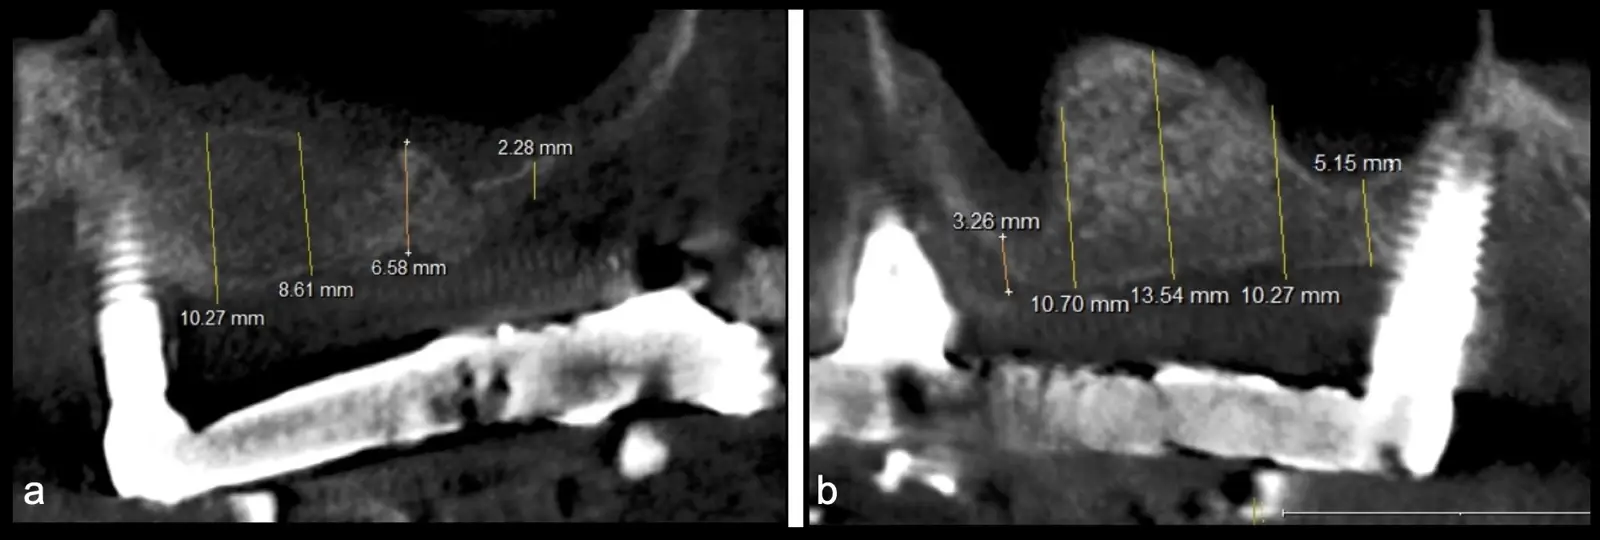

La técnica se inicia con la colocación de anestesia infiltrativa, posteriormente se realiza una incisión crestal o paracrestal con posibles liberantes verticales que deben de estar alejadas por lo menos 5 mm de los límites de la futura ventana y sobrepasar la línea mucogingival. Se realiza una elevación de colgajo, se inicia la antrostomía y antroplastía. Para ello, se emplea el inserto redondo diamantado de corte al momento de delimitar los bordes de la ventana de acceso. Luego se cambia al inserto aserrado liso de calibre fino con superficie diamantada, para profundizar y eliminar el hueso en el contorno de la ventana. Una vez que se traslucen los tejidos, se puede optar por el retiro de la tapa ósea o el levantamiento de ésta junto con la membrana.

Se inicia la elevación de la membrana de Schneider con el inserto redondeado no cortante en forma de disco, empleando movimientos suaves. El levantamiento puede complementarse con elevadores convencionales, siguiendo la dirección mesiodistal. La fase de desprendimiento inicia con el piso y sigue hacia la pared mesial para terminar, y de ser necesario, hacia la pared posterior. Existen diversos insertos con angulaciones y longitudes para mayor accesibilidad16 (Figura 1).

Una vez elevado el piso sinusal según la planificación se realiza la evaluación clínica de la integridad de la membrana y de posibles desgarros a través de la maniobra de Valsalva.24 Consiste en pedir al paciente que respire profundamente y retenga el aire, cerrar la boca, apretar la nariz con los dedos y forzar la salida de aire. Al final de la prueba, es necesario mantener la presión entre 10 a 15 segundos. Se identificará la movilidad de la membrana y la ausencia de burbujas de aire para corroborar que no hay perforaciones. Dependiendo de la decisión clínica se puede optar por adicionar en la superficie de la membrana de Schneider membranas de colágeno o de plasma rico en fibrina (PRF) para dar mayor soporte durante la inserción del biomaterial de relleno óseo (Figura 10).